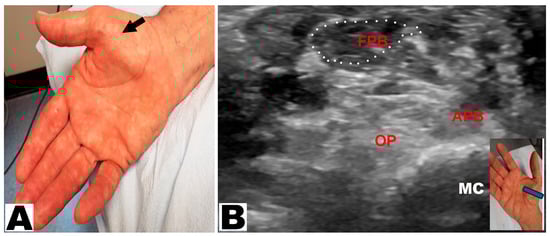

Thenar muscle atrophy was observed in a total of 226 hands (197 patients unilateral and 29 patients bilateral) (Table 3). Of the 226 hands, thenar muscle atrophy was partial in 174 (77.0%) hands and total in 52 (23.0%) hands (Figure 2A,B). The APB and OP muscles were weak in all (100%) hands. A prominent FPB muscle was noted in 44 (19.5%) hands, all of which had partial thenar muscle atrophy (Figure 3A,B and Figure 4A,B). A total of 217 (96.0%) hands had sensory loss.

Figure 3. (A) Partial thenar atrophy: the flexor pollicis brevis muscle is visible (arrow) with atrophy of the abductor pollicis brevis muscle. (B) Ultrasound depicts partial thenar atrophy. The intact flexor pollicis brevis (FPB) muscle is encircled. APB: abductor pollicis brevis muscle. OP: opponens pollicis muscle. MC: metacarpal.

Figure 4. (A) Partial thenar atrophy with hypertrophy of the flexor pollicis brevis (FPB) muscle (oblique arrow). (B) Ultrasound study confirms partial thenar atrophy with a hypertrophic FPB muscle (encircled) and severe atrophy of the APB and OP muscles. The blue insert denotes the position of the ultrasound probe. APB: abductor pollicis brevis muscle. OP: opponens pollicis muscle. MC: metacarpal.